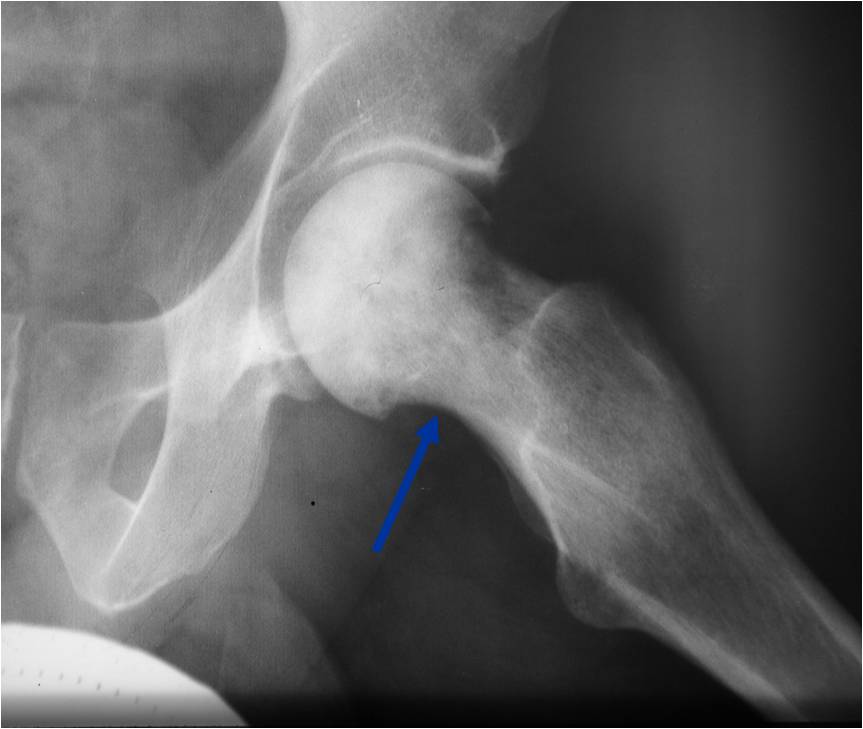

- Lower extremities involved most often especially femur and pelvis

- Permeative or moth eaten bone destruction (55%)

- Metadiaphysis (75%)

Permeative Moth eaten Lesion